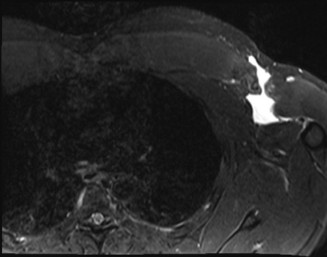

- MRI (Magnetic Resonance Imaging): The gold standard. MRI precisely identifies the location of rupture (humeral avulsion, musculotendinous, muscle belly), extent of retraction, degree of muscle degeneration (fatty infiltration in chronic cases), and associated injuries. It also helps differentiate partial from complete tears.

A pre-operative MRI axial view demonstrating a complete pectoralis major tendon avulsion from the humeral insertion (white arrow) with significant retraction. -